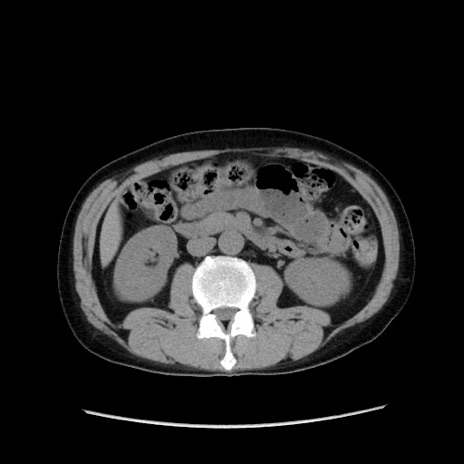

症例37(横断像)

【症例】40歳代 男性

【主訴】腹痛

【現病歴】4時間ほど前に電車に乗車中に臍部上より腹痛出現。徐々に増悪し起立困難となり、救急外来受診。生ものは数日食べていない。今朝お雑煮を食べた。

【身体所見】BT 36.8℃、BP 117/84mmHg、HR 91/min、SpO2 97%、苦悶様、腹部:臍上部広範囲圧痛あり、反跳痛±

【データ】WBC 8100、CRP 0.03